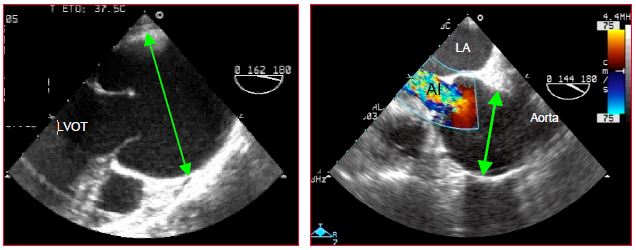

Marfan syndrome is an autosomal dominant disease of the connective tissue whose prevalence is 0.3%. Dilation of the aortic root and ascending aorta is observed in 60-80% of these patients (Videos and Figure 15.52). Dissection is a common complication (see Chapter 18 Ascending aorta) [1].

Video: Aortic regurgitation in the same case of Marfan syndrome.

Figure 15.52: Marfan syndrome A: significant dilation of the aortic root – the aortic valve is bicuspid – it does not open completely during systole. B: severe aortic insufficiency (AI) in a case of Marfan syndrome with dilation of the aortic root.